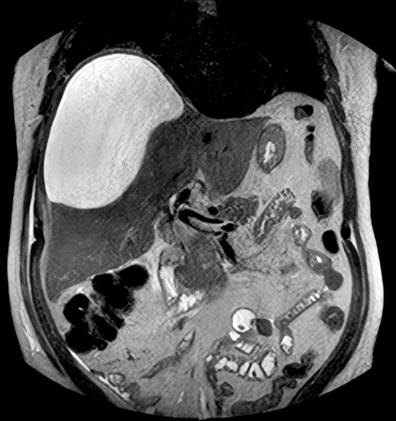

Se tomó una ecografía abdominal en la que se describió dilatación de la vía biliar con la medición de la vía derecha: 5 mm, la izquierda: 4,8 mm y en la confluencia: 5,3 mm. También se describió una escasa cantidad de gas a nivel de las vías biliares intrahepáticas. Se tomó una colangiorresonancia con hallazgo de alteración focal en la región subcapsular del segmento VI hepático con imagen de 34 x 31 x 37 mm, de contenido heterogéneo e imágenes similares de menor tamaño, 10 y 13 mm, en el segmento VIII, sospechosas de abscesos; se documentó también líquido subcapsular hepático en el lóbulo derecho (112 mL) (Figura 1) y dilatación de la vía biliar intrahepática con imágenes de microlitiasis en el conducto hepático derecho cerca a la confluencia y en el segmento intrapancreático del conducto colédoco. Pasadas 48 horas se realizó una resonancia magnética de abdomen con hallazgo de aumento del volumen de la colección subcapsular hepática (Figura 2), por lo que el paciente fue llevado a inserción de un catéter multipropósito. En el procedimiento se realizó un drenaje de 1600 mL de líquido de aspecto biliar purulento. El paciente continuó por 5 días con drenaje biliar de 350-500 mL diarios por el catéter multipropósito y con signos de respuesta inflamaría, por lo que fue llevado a CPRE.

Figura 2 Resonancia magnética de abdomen. Se observa el aumento del volumen del bilioma. Archivo de Imágenes del Hospital Universitario Hernando Moncaleano Perdomo de Neiva.